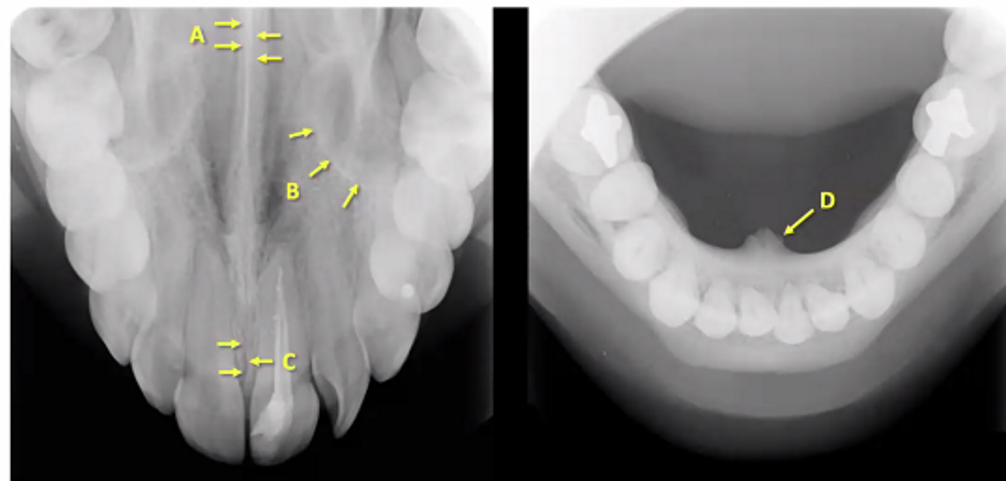

A

nasal septum/vomer (white so bony)

B

medial wall of maxillary sinus

C

medial or midline palatal suture

D

genial tubercle